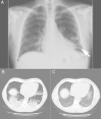

On chest x-ray there were clear interstitial nodular opacities at both bases, more evident on the left side (Fig. 1A).

Image 1A - Chest x-ray: interstitial nodular opacities at both bases, but more evident on the left side (arrow). Image 1B - High resolution CT scan: bilateral areas of parenchymal consolidation with air bronchograms in posterior-basal regions and the lingula strongly suggesting a pneumonic process. Image 1C - ground glass opacity in the lung bases and no evidence of parenchymal consolidation (1 month follow-up).

The high-resolution chest CT scan revealed that “(...) areas of parenchymal consolidation with air bronchograms in posterior-basal regions of both lungs and in the lingula, strongly suggestive of pneumonic process (…)” (Fig. 1B).

After one month the patient comes for consultation asymptomatic. The follow-up thoracic CT revealed images of ground glass opacity in the lung bases, with no evidence of parenchymal consolidation (Fig. 1C), which was quite an improvement. At this time slow tapering of prednisolone (5mg / month) was started. By the 3rd. month of follow-up all normal physical activities had been resumed, with no evidence of any changes on chest films or CT scan.